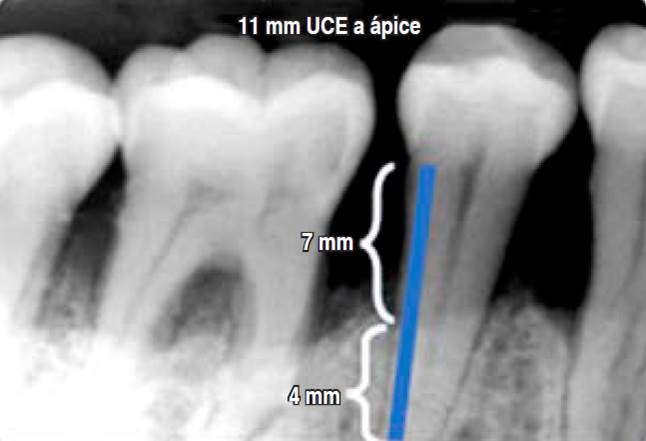

Evidencia indirecta de progresión: al carecer de datos previos de la pérdida ósea radiográfica o de inserción clínica, se puede determinar el grado por el porcentaje de pérdida ósea presente en el diente más afectado dividida entre la edad del paciente. El grado A corresponde cuando el resultado es menor de 0.25, el grado B abarca de 0.25 a 1.0, y el grado C corresponde a más de 1.0 (Figura 6).19

Figura 6 Obtención de evidencia indirecta de progresión en el diente 45 más afectado. Se mide la longitud radicular de la unión cemento esmalte (UCE) al ápice = 11 mm; posteriormente se mide de la UCE a la cresta ósea = 7 mm. Utilizando una regla de tres (7 × 100/11) se determina que este diente tiene 63% de pérdida ósea. Para la obtención del grado de progresión: 63% de pérdida ósea es dividido por la edad del paciente (50 años), lo que da como resultado 1.26 que corresponde a una tasa de progresión rápida, grado C.